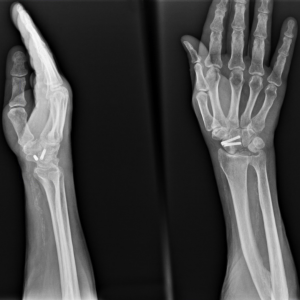

Снимок после укорочения лучевой кости

Элегантный способ фиксации остеотомии скобкой.

При обнаружении некроза полулунной кости почти всегда я рекомендую начинать с остеотомии лучевой кости. Это относительно безопасная и весьма эффективная операция. Она заключается в пересечении лучевой кости (пилой или остеотомом) с последующей ее фиксацией. При этом сам кистевой сустав и кости запястья даже не затрагиваются. Плюсы в том, что мы, не вмешиваясь в поврежденный сустав, можем значительно улучшить его функцию.

Вернемся к нашей героине, которая столкнулась с проблемой запястья накануне свадьбы. За месяц до намеченной даты была выполнена операция — остеотомия лучевой кости.